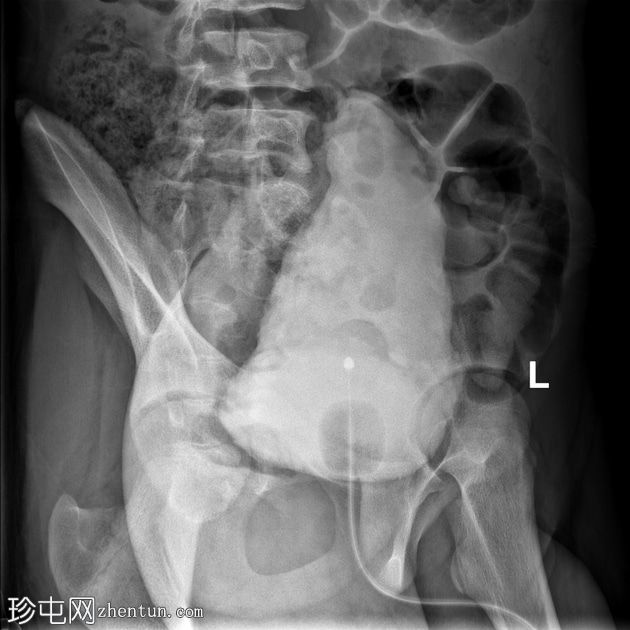

荧光透视

正面

左

通过导尿管注入造影剂后,可见膀胱延长,膀胱壁不规则,呈小梁状,并有多个大小不一的外囊。

排尿后序列中可见残余尿液。

本病例展示了

神经

源性膀胱的临床和放射学特征。